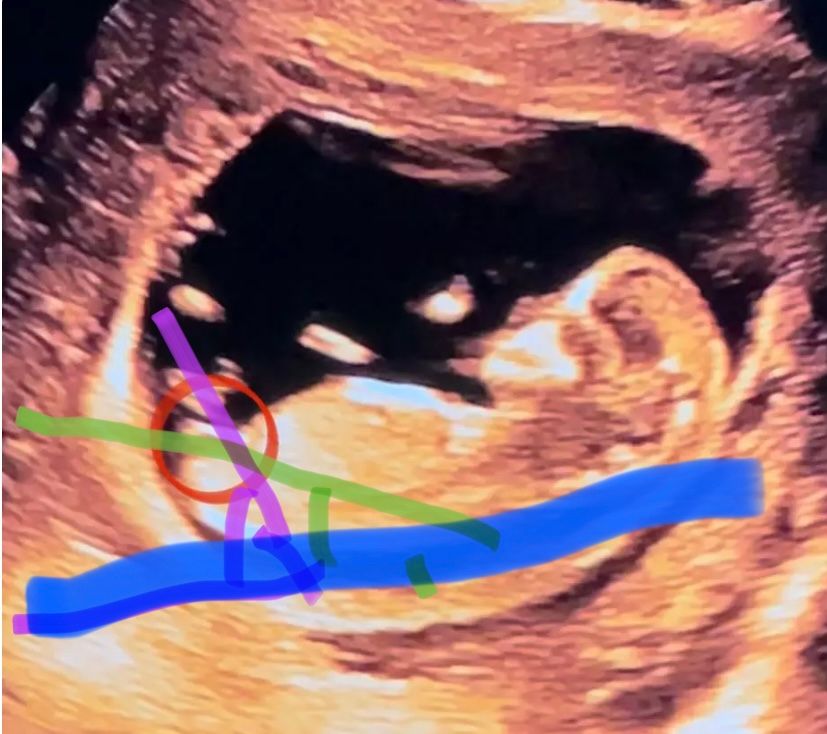

100% девочка. Это же не гадание на кофейной гуще, а достоверный метод исследования) Полосочка-это половой бугорок, если «встанет» наверх углом более 30 градусов от параллели тела Изображение , то потом преобразуется в половой член, а если вниз «ляжет», то клитор. Синяя-параллель тела, а зелёненьким ваш угол к ней, получается менее 30 градусов, значит дамочка. А если бы было более 30- как фиолетовым, тогда бы был парень)

да, если половой бугорок параллельно позвоночнику, как у вас, то девочка.

Да, тоже больше видится девочка. Белая полосочка - это половой бугорок.